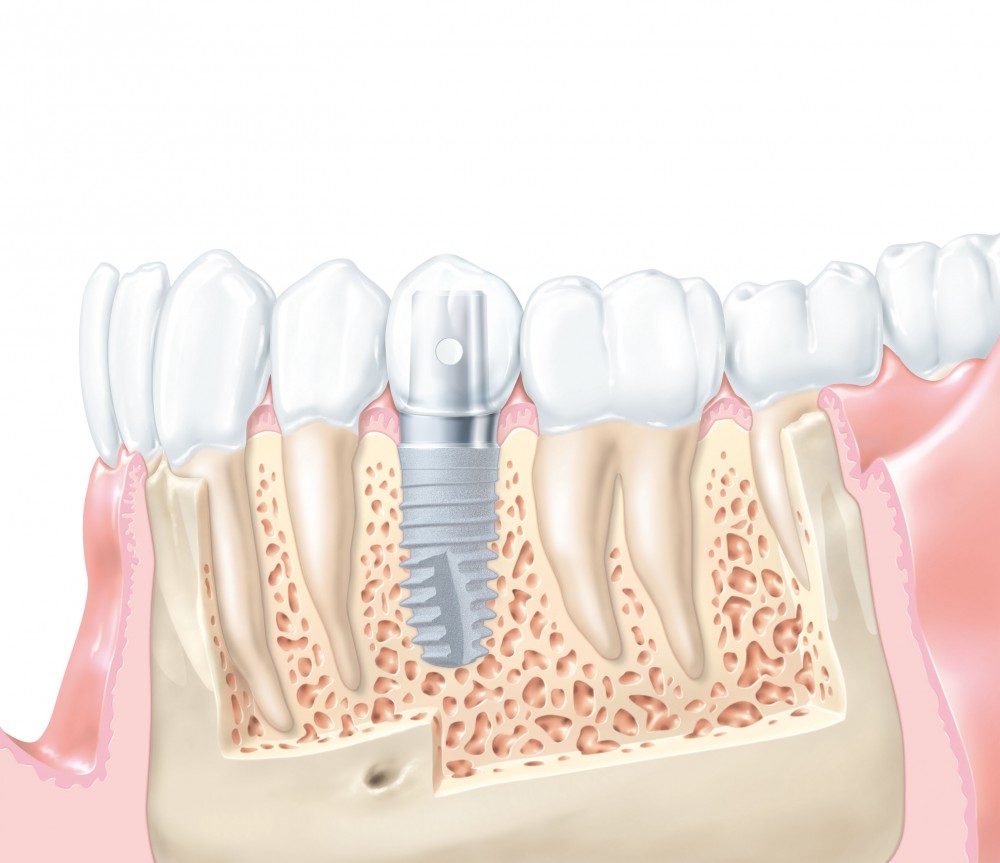

Фото и примеры имплантации зубов при пародонтите

Раздел: Необычные решения